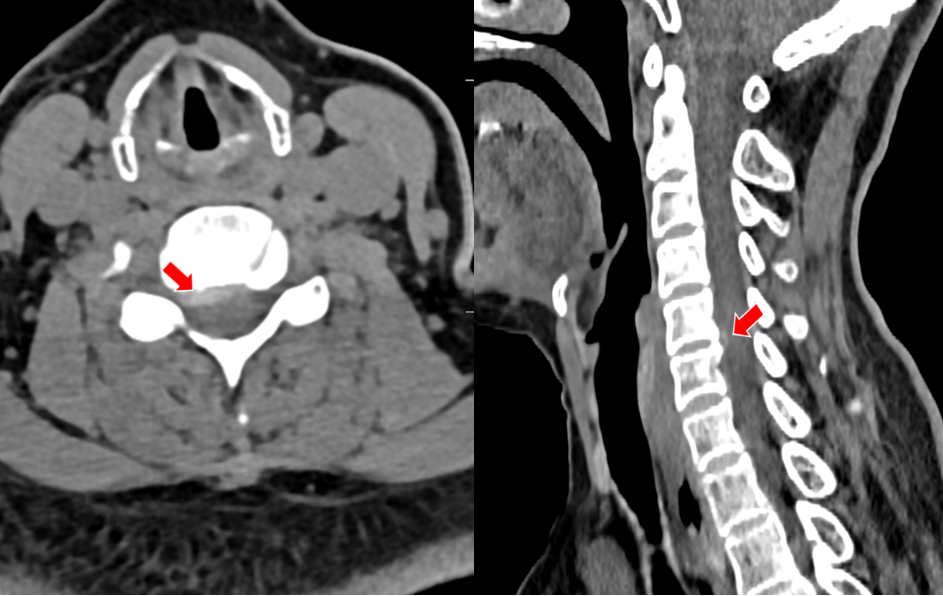

无独有偶,我院骨科还为一对姐弟完成了一组颈椎后路手术。姐弟俩吕艳、吕飞(化名)均患有“颈椎后纵韧带骨化症”。弟弟吕飞今年40岁,是位企业白领。别看他年龄不大,其实已多年饱受颈椎病之苦。由于长期伏案工作,这些年他常常感觉自己四肢乏力,走路像踩在棉花上一般,像系纽扣、写字这样的活动也逐渐无法完成,这让他很是着急。通过亲友介绍,他找到姜为民主任寻求帮助,姜主任在仔细的查体和阅片后,判断吕飞的颈椎后纵韧带骨化节段多,症状重,应当尽早手术,解除对脊髓的压迫。

(颈椎CT提示患者C3-6椎体后纵韧带骨化明显,椎管狭窄显著)

(颈椎CT显示张先生C2-6椎体后纵韧带广泛骨化,椎管狭窄明显)

(颈椎MRI提示C2-6椎管狭窄,脊髓受压严重)